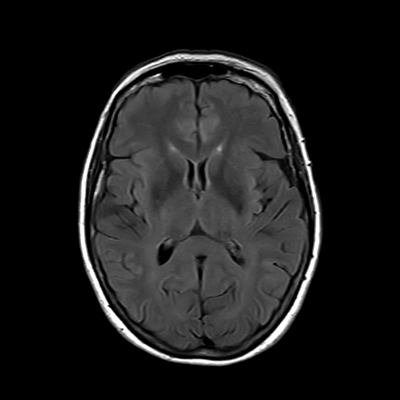

You also obtain an MRI of his brain once it's clinically safe to do so.

MRI brain (FLAIR)